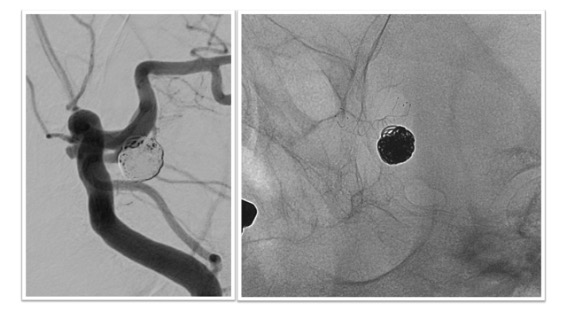

フローダイバーター治療実例(*患者様の許可を得て掲載しています)

大型内頸動脈(IC)動脈瘤

大型IC動脈瘤に対してフローダイバーターによる治療を実施。フローダイバーターは動脈瘤の根本をカバーする形で留置されました(右図)。術後は抗血小板薬の内服がしばらく必要となりますが、動脈瘤はその後半年ほどで閉塞しています。